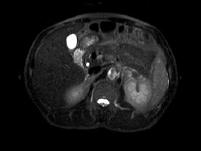

问题 男,52岁,下肢无力伴多饮多尿2?年余,实验室检查:低血钾,血醛固酮水平及24小时尿醛固酮定量超过正常值,MRI检查如图所示,应诊断为()

选项 A.左肾上腺囊肿 B.左肾上腺腺瘤 C.左肾上腺嗜铬细胞瘤 D.左肾上腺髓脂瘤 E.左肾上腺转移瘤

答案 B